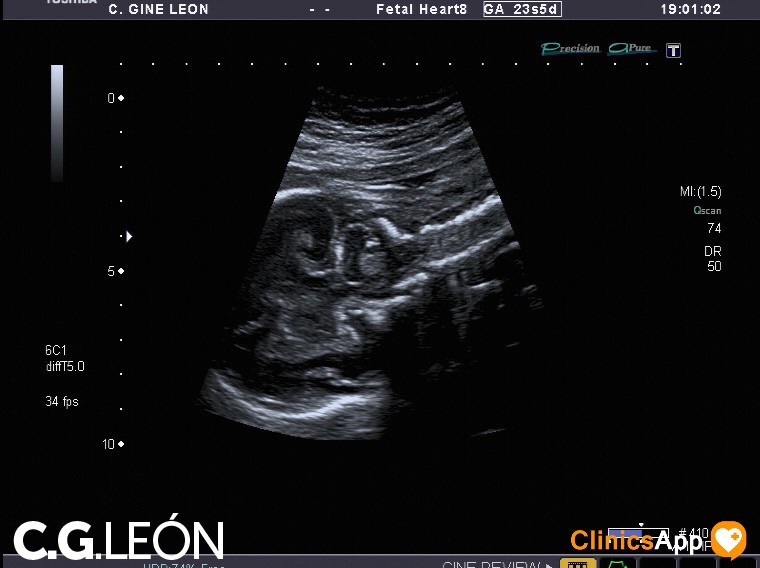

Aquí las fotos de la quinta ecografía, nada que destacar excepto que la ginecóloga estaba de mala leche y no se esmeró demasiado en las fotos. Hay una en la que se ve una mano, en directo se distinguía mejor, claro, porque se vio abierta como en la foto y luego la cerró. Pero por lo general encuentro de difícil interpretación este lote de fotos.